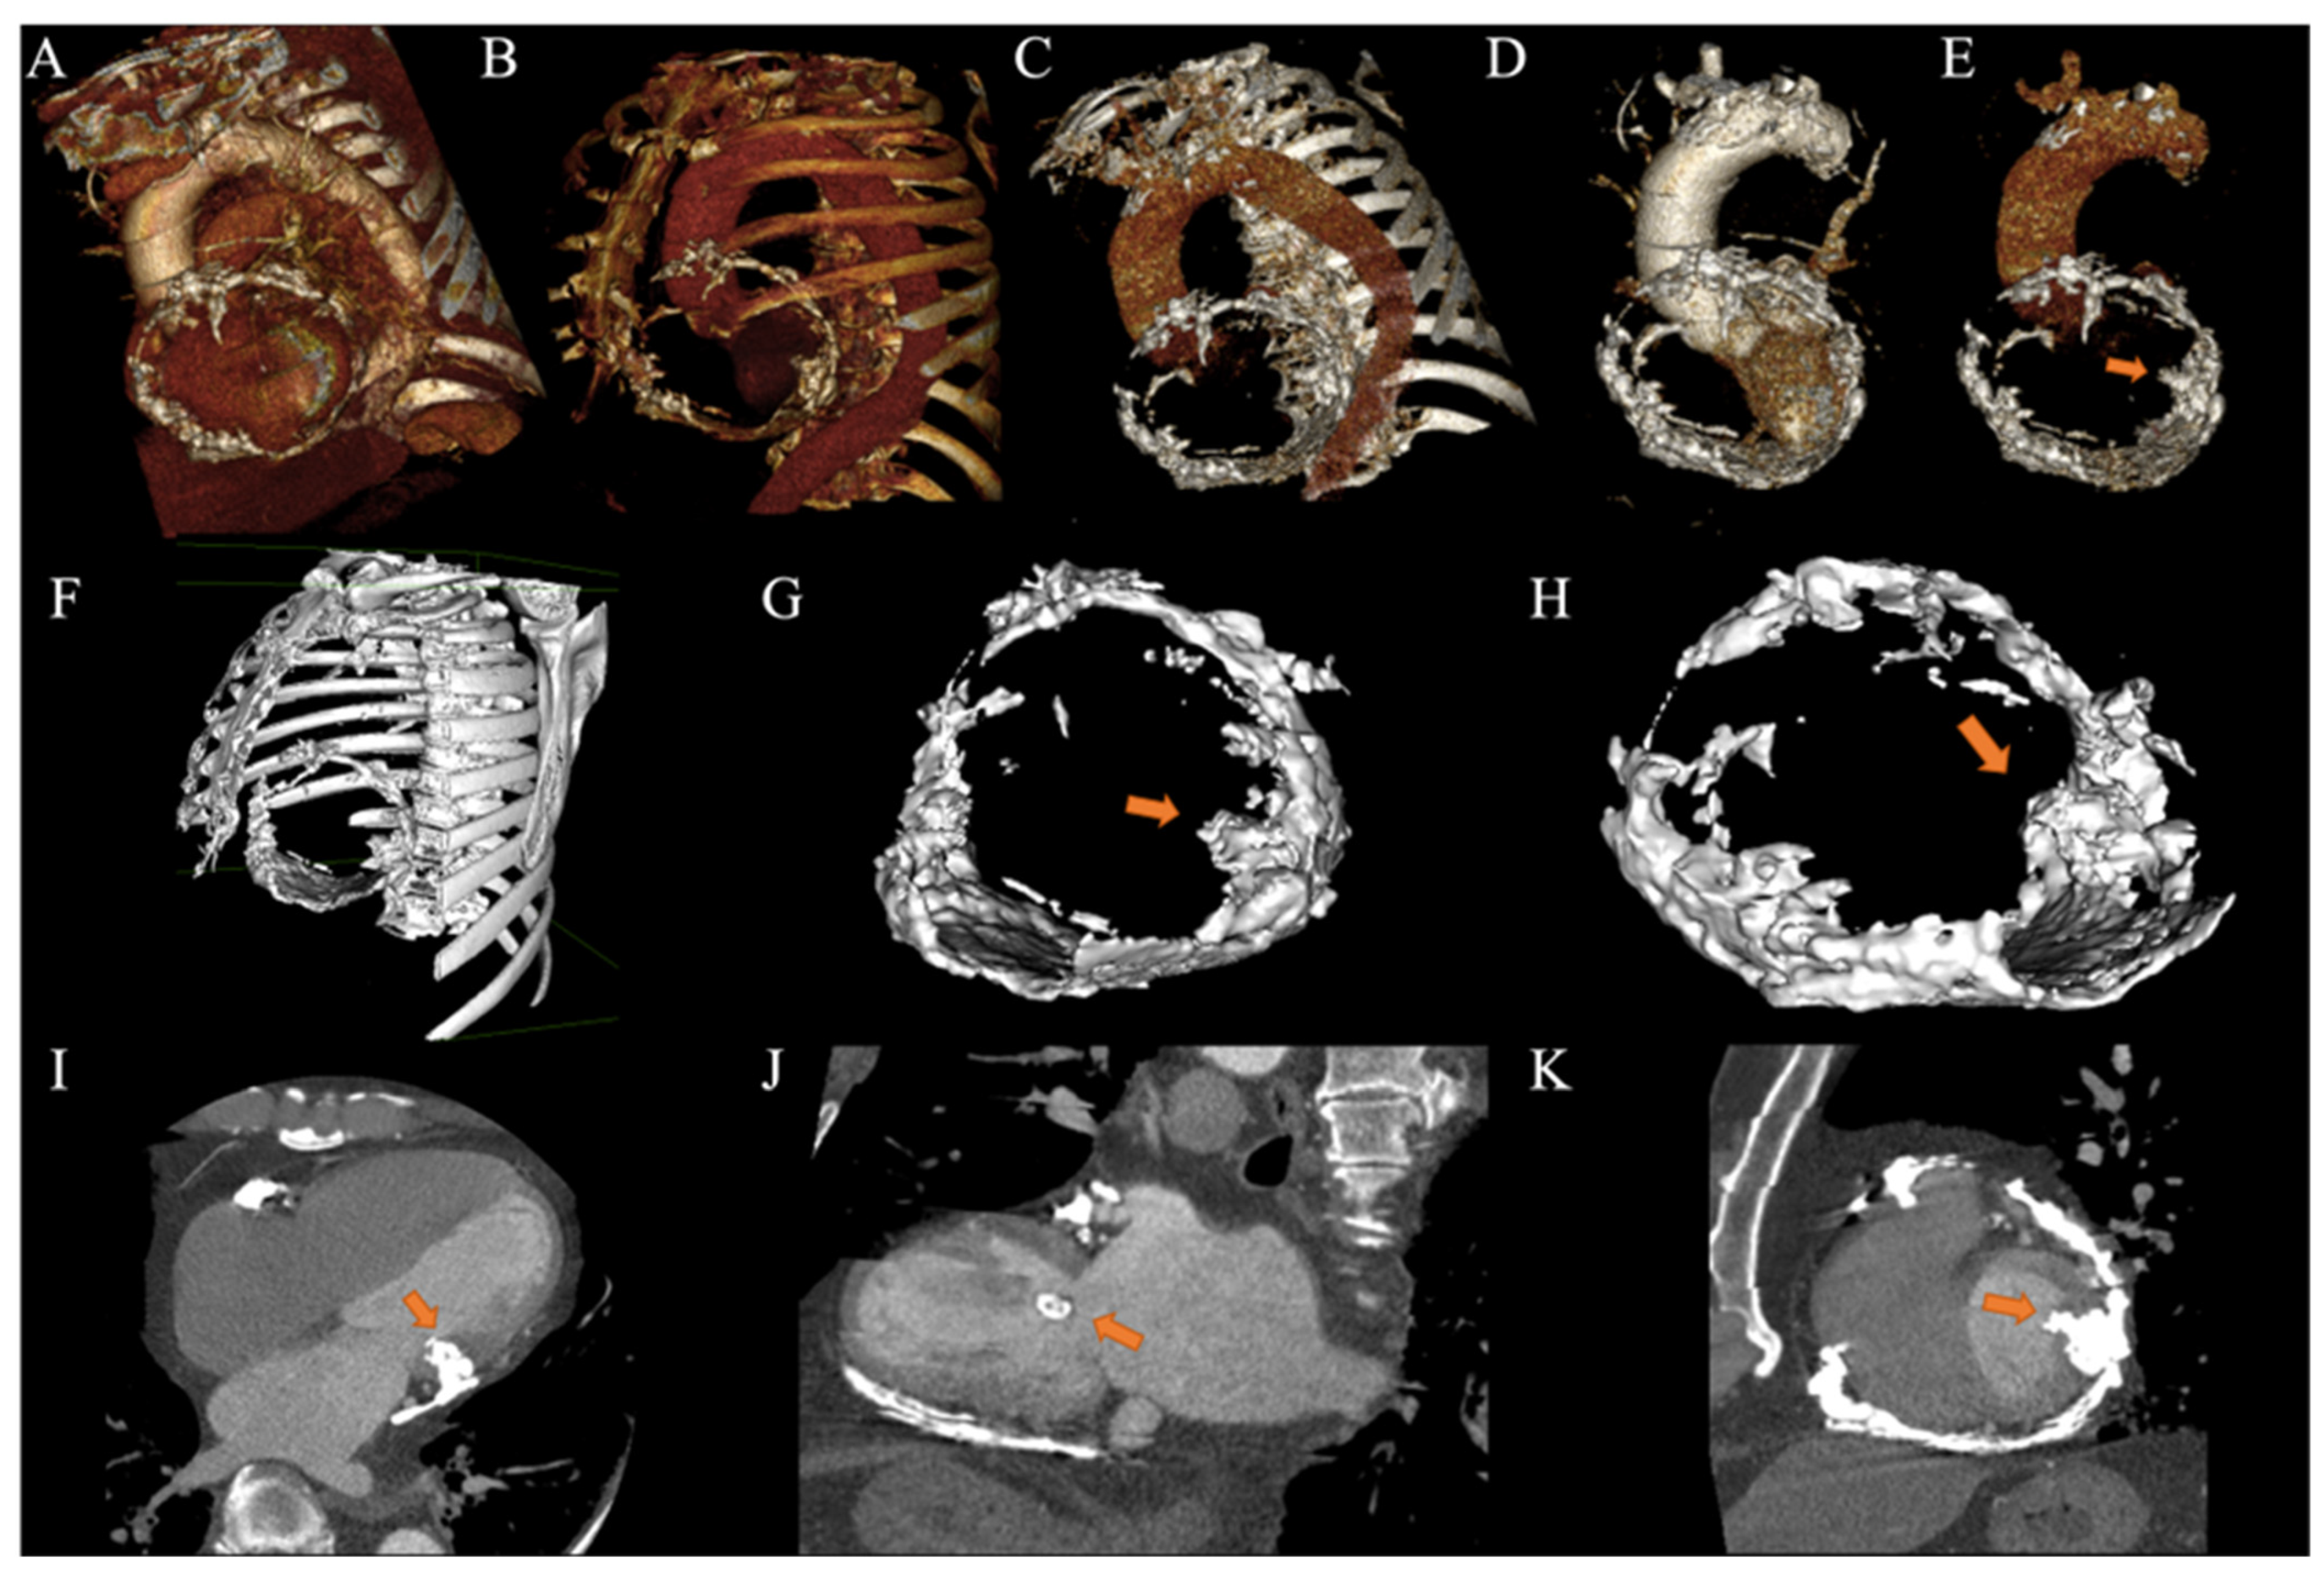

2. Case Presentation

2.3. Clinical Findings